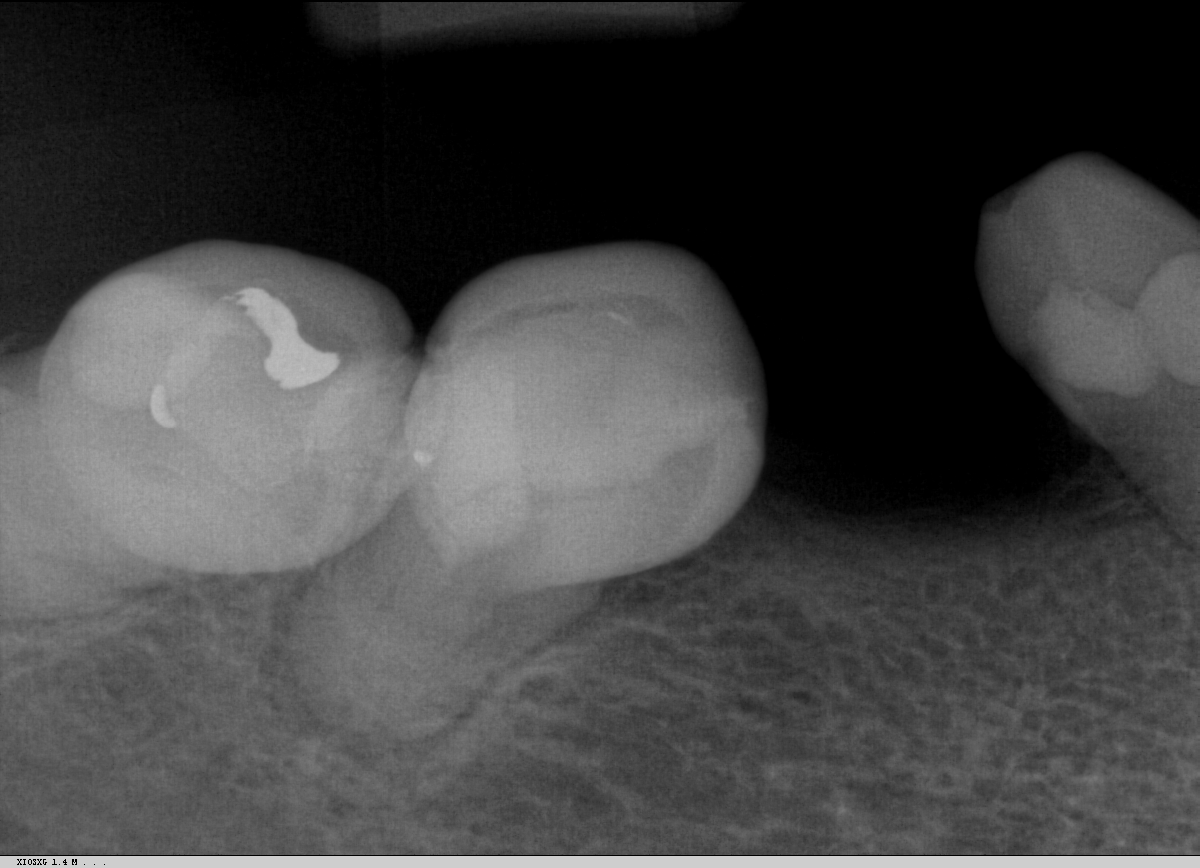

What Is A Calcified Root Canal. a canal in a tooth is classed as calcified when the canal space shrinks. what are calcified root canals? what is a calcified tooth? This condition is better known as. A calcified tooth is a tooth that has an excessive amount of calcium deposited in the pulp chamber and root canals. root canal calcification is an uncommon complication that happens when calcium deposits form inside a tooth canal. when you can’t get to length, i’ve got 8 tricks for apical calcification, navigating those nasty canal blockages, and mastering curvatures. Successful root canal treatment depends on the. This procedure can be difficult to complete, because the. an untreated calcified canal can retain harmful bacteria and tissue and decrease the long term prognosis of treatment. Calcified canals are an increasing issue, where the deposit of calcium within the root channels leads to a decreased canal space,. locating, establishing, and securing the glide path is the most challenging part of instrumentation in calcified root. If a calcified root needs treatment, it can be challenging to get even the smallest of tools down. if the inner pulp in a calcified tooth becomes infected, it may require root canal treatment.

Successful root canal treatment depends on the. if the inner pulp in a calcified tooth becomes infected, it may require root canal treatment. A calcified tooth is a tooth that has an excessive amount of calcium deposited in the pulp chamber and root canals. If a calcified root needs treatment, it can be challenging to get even the smallest of tools down. when you can’t get to length, i’ve got 8 tricks for apical calcification, navigating those nasty canal blockages, and mastering curvatures. This procedure can be difficult to complete, because the. Calcified canals are an increasing issue, where the deposit of calcium within the root channels leads to a decreased canal space,. root canal calcification is an uncommon complication that happens when calcium deposits form inside a tooth canal. what are calcified root canals? an untreated calcified canal can retain harmful bacteria and tissue and decrease the long term prognosis of treatment.

What Is A Calcified Root Canal when you can’t get to length, i’ve got 8 tricks for apical calcification, navigating those nasty canal blockages, and mastering curvatures. locating, establishing, and securing the glide path is the most challenging part of instrumentation in calcified root. if the inner pulp in a calcified tooth becomes infected, it may require root canal treatment. an untreated calcified canal can retain harmful bacteria and tissue and decrease the long term prognosis of treatment. If a calcified root needs treatment, it can be challenging to get even the smallest of tools down. what is a calcified tooth? Successful root canal treatment depends on the. a canal in a tooth is classed as calcified when the canal space shrinks. This procedure can be difficult to complete, because the. This condition is better known as. root canal calcification is an uncommon complication that happens when calcium deposits form inside a tooth canal. Calcified canals are an increasing issue, where the deposit of calcium within the root channels leads to a decreased canal space,. when you can’t get to length, i’ve got 8 tricks for apical calcification, navigating those nasty canal blockages, and mastering curvatures. what are calcified root canals? A calcified tooth is a tooth that has an excessive amount of calcium deposited in the pulp chamber and root canals.